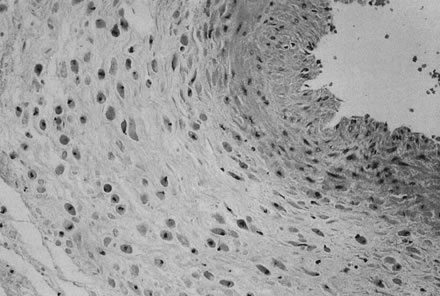

In addition to these large-scale placental lesions, chronically abnormal uteroplacental vascular perfusion may impair the growth and development of the placenta (Fig 16). Alternatively, it may lead to diffuse villous lesions that cannot be identified grossly. Scarred, shrunken, fibrotic, and hypovascular villi, with reduced placental capillary number and/or caliber, may be caused by capillary destruction by abnormal turbulent uteroplacental flow (Fig. 17).130 Villous capillary damage may lead to fetomaternal hemorrhage. Fetomaternal hemorrhages in the midtrimester (when the barrier between maternal and fetal bloodstreams is still comparatively thick and “sturdy”) are more frequent in hypertensive pregnancies.131 Chronic placental perfusion injury and/or nutritional deprivation may impair terminal villous arborization. The small placenta with uteroplacental vascular lesions may often show histologic increased intervillous volume and decreased villous parenchymal volume, smaller terminal villi, and apparently sparser villous numbers. The placental mass, in these circumstance, may simply fail to develop. The net effect of poor placental growth is a reduced total villous capillary bed. This anatomy would be analogous to an emphysematous lung. Just as significant to the fetus is the effect of reduced placental capillary bed on total peripheral resistance. The smaller placental vascular tree would have increased placental resistance and cause increased cardiac work. Five hundred milliliters per minute of fetal cardiac output is directed to the placenta; the cardiac work effects may be dramatic. An indirect reflection of umbilical-placental resistance is the umbilical systolic/diastolic ratio. This ratio approaches infinity and end-diastolic flow in the umbilical artery may be negative when the placental capillary bed is reduced by more than 50%.132 A reduction in the total fetoplacental capillary bed is paralleled by a reduction in fetoplacental volume. Reduced fetal blood volume can result in a reduced fetal glomerular filtration rate and oligohydramnios.133

Fig. 16. A. Placenta at 26 weeks' gestation with “accelerated maturation” due to preeclampsia (hematoxylin and eosin, ×10). B. Unlike normal syncytial knots, exaggerated syncytial knots project above the surface of the villus (hematoxylin and eosin, ×40).